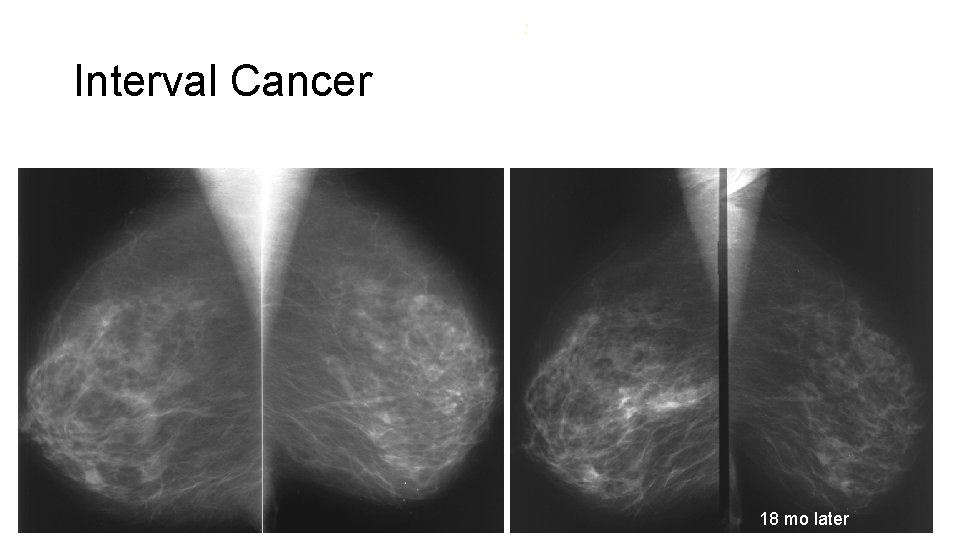

Interval Cancer Rate • A comparison of interval cancer rate gives an indication of success of thresholds used to intervention • The higher the interval cancer rate, the less successful the screen • Intrerval cancer: • Cancer, diagnosed between screenings, not visible in mammograms of previous screening round • Cancer, diagnosed between screenings, interpreted as negative, benign or probably benign on previous screening

: Interval Cancer 18 mo later